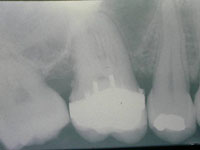

Fig. 1

Vista intra-bucal por oclusal do dente 26 mostrando as cúspides mésio-vestibular e mésio-palatina fragilizadas.

Fig. 2

Vista por vestibular após a redução das cúspides.

O dente 16 apresentava apenas duas cúspides remanescentes e fragilizadas, as quais precisaram ser reduzidas por desgaste (Fig. 1). Após a redução cuspídea, restou uma coroa clínica curta e com assoalho pulpar plano. Devido a essas condições não havia a possibilidade de preparar uma caixa oclusal, os degraus proximais que determinam uma cavidade MOD pois a polpa seria atingida , assim como, estrutura para reter uma coroa total. (Fig. 1, 2 e 3).